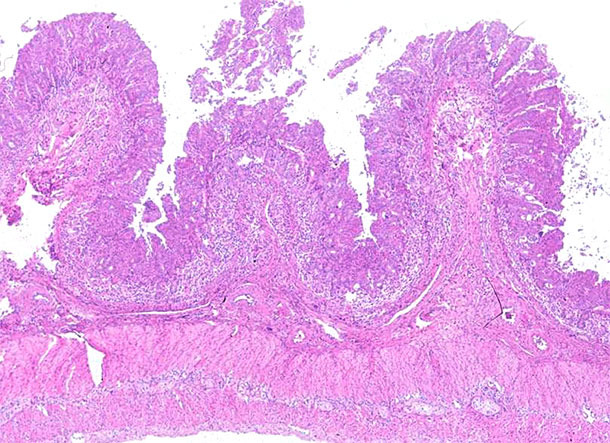

Cabe destacar que los problemas entéricos se encontraron con frecuencia en granjas afectadas por PCV2-SD. No obstante, no estaba claro el mecanismo exacto por el cual estos animales enfermos tenían diarrea. Por un lado, la inmunosupresión sistémica vinculada a PCV2-SD sería una de las razones principales para desencadenar el efecto de los patógenos entéricos existentes en la granja, que pueden no expresarse a menos que el sistema inmune esté comprometido. Por otro lado, el resultado patológico de PCV2-SD en una parte de los animales incluye un grado variable de enteritis granulomatosa (fotografías 1 y 2), que causaría diarrea debido a la alteración de la permeabilidad de la barrera intestinal. En este escenario, la llegada de las vacunas PCV2 causó una disminución radical de cerdos y granjas que presentaban signos clínicos y lesiones de PCV2-SD y, por tanto, la concomitancia de la infección viral con otros patógenos entéricos disminuyó significativamente.

Fotografía 1. Íleon. Depleción de linfocitos marcada e inflamación granulomatosa de las placas de Peyer en el íleon de un cerdo afectado por enfermedad sistémica asociada a PCV2. Tinción de hematoxilina y eosina.